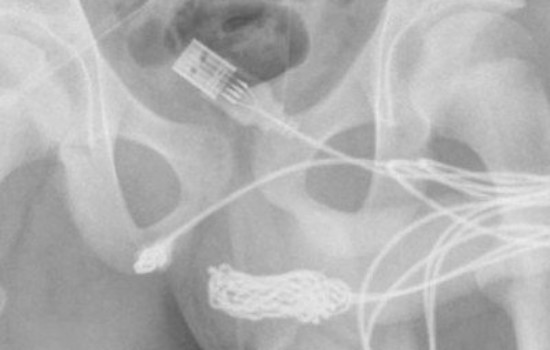

Um exame de raio-X revelou o tamanho exato e a posição do cabo. O adolescente foi encaminhado para a sala de cirurgia e os cirurgiões cortaram os músculos ao redor do pênis e do escroto para removeram o cabo.